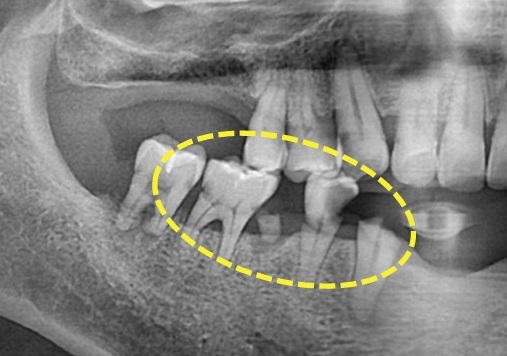

세심하고 정확하게 확인하기 위해

파노라마와 3D CT

구강 내 사진을 통해

치료 계획을 세웠습니다.

구상 상태를 보면

전체적으로 잇몸이 많이 약해져있는데요.

충치도 심하고

치아도 많이 파절되어 있는 모습입니다

치아 뿌리 주변으로

까맣게 보이는 게 염증입니다.